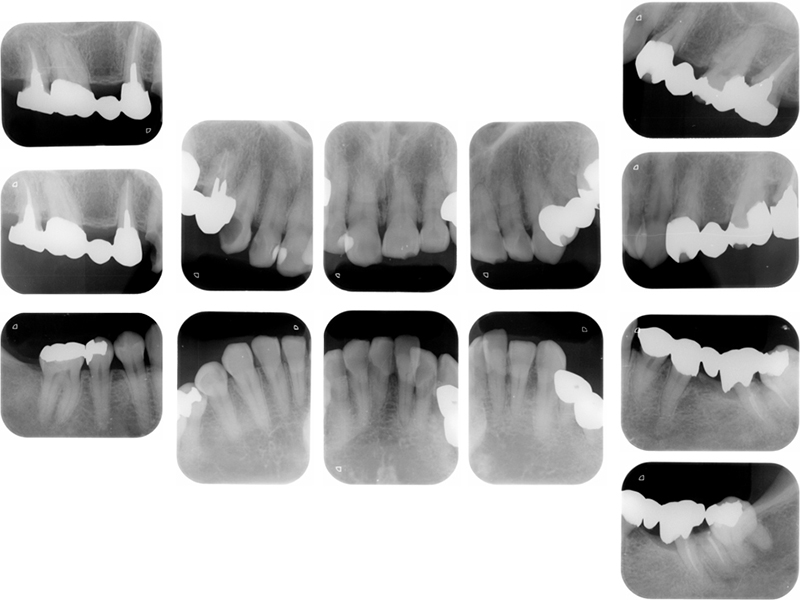

▼ ケース5 下顎前歯部叢生症例

初診時X線写真